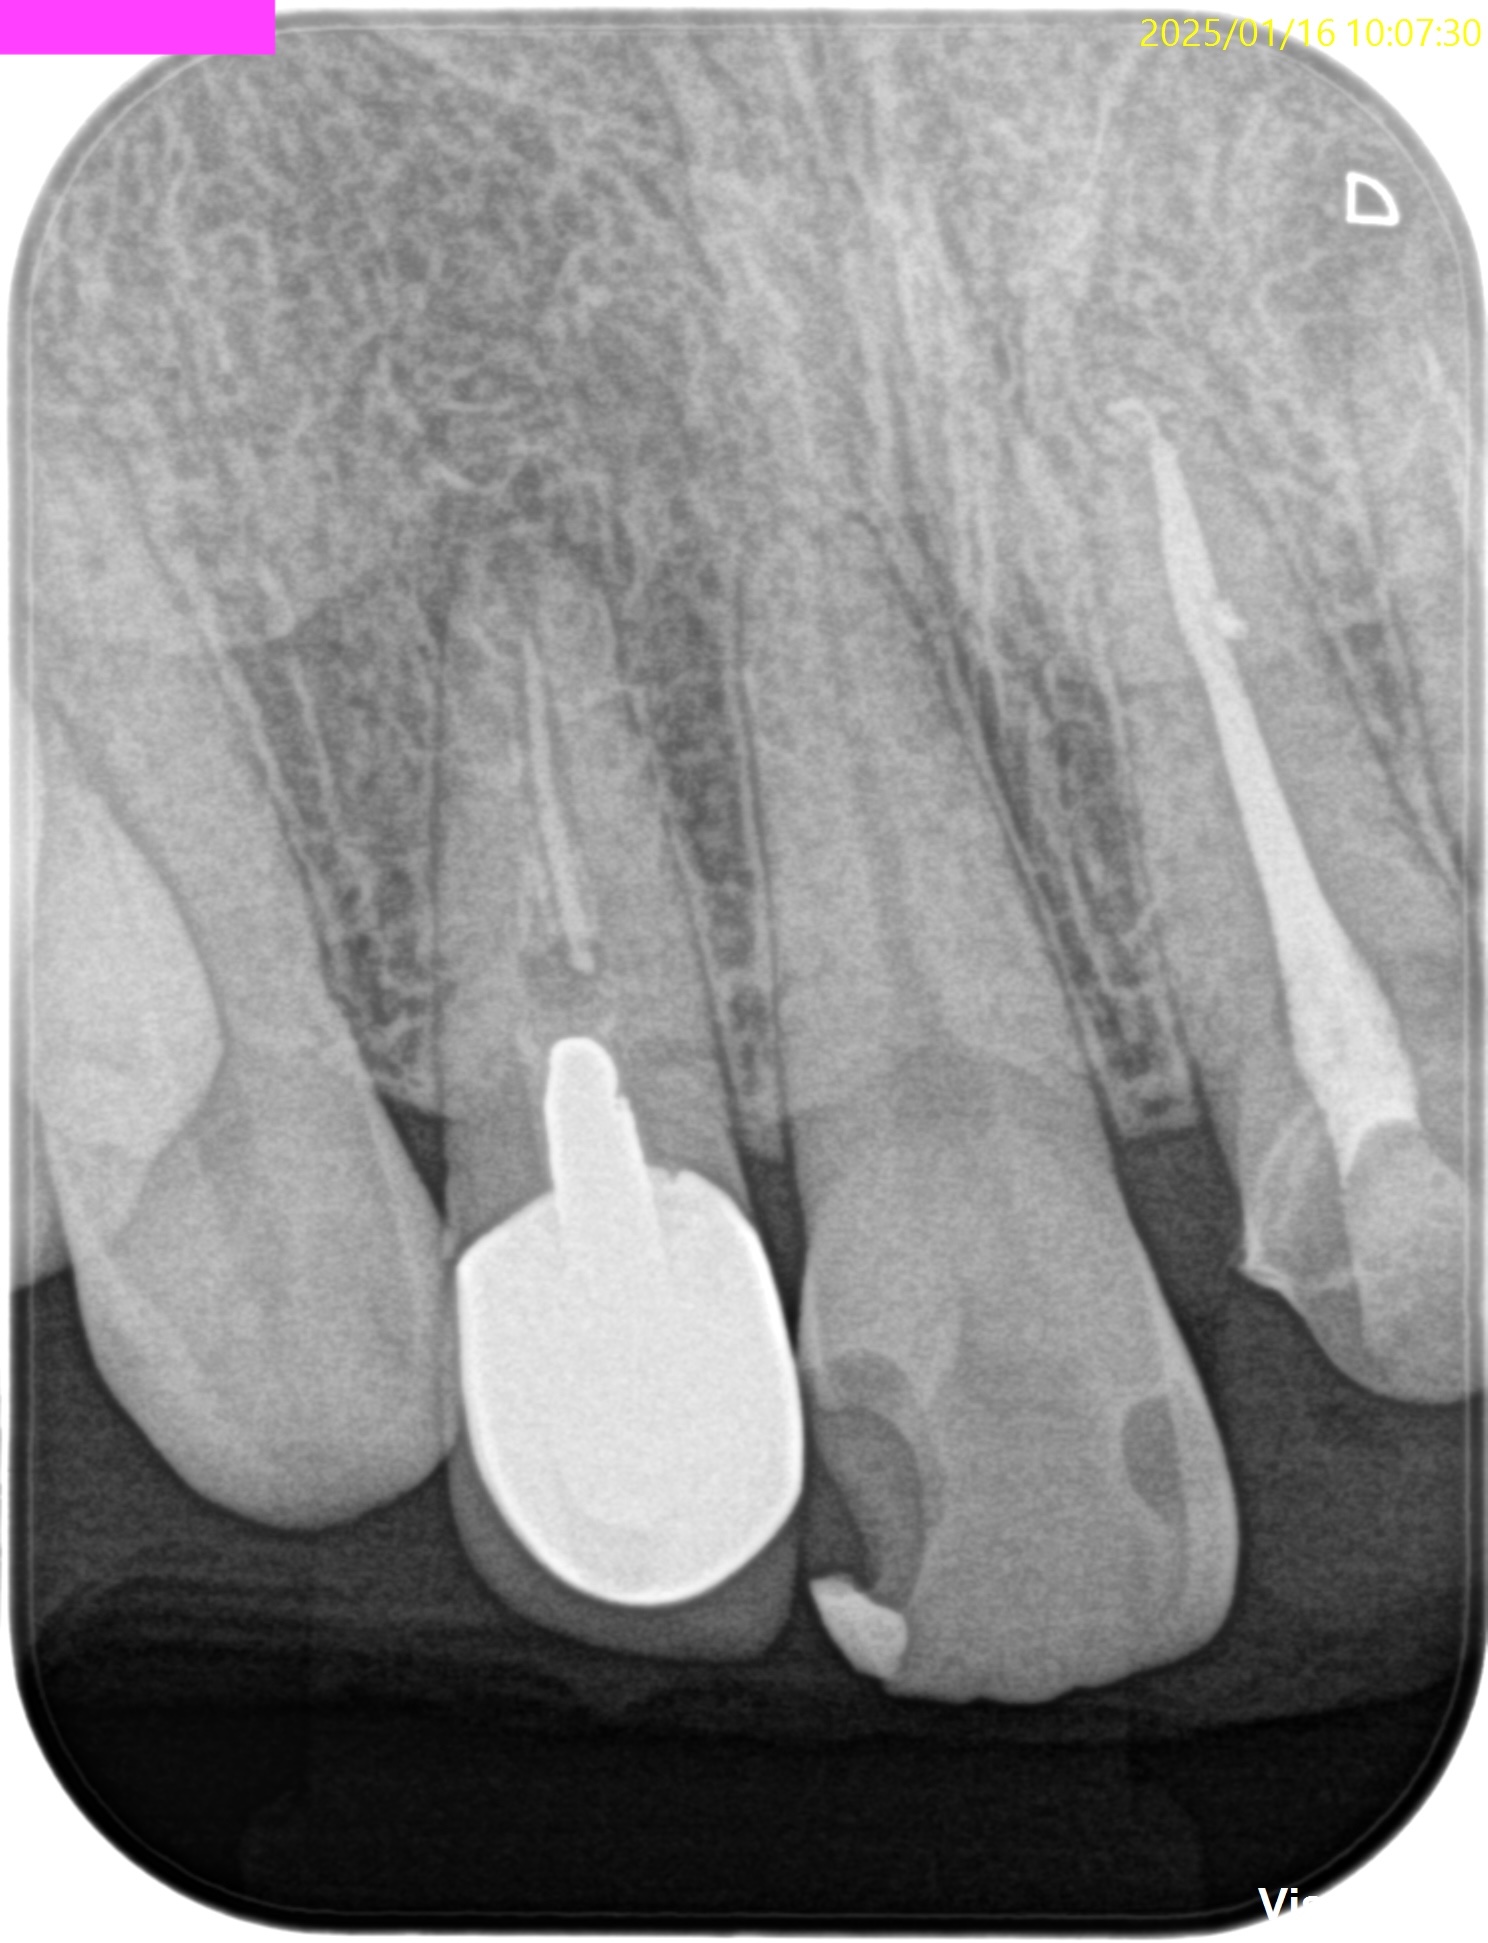

PA(2025.1.16)

#7,10はほぼ治療がなされていない。再根管治療が必要な案件だ。